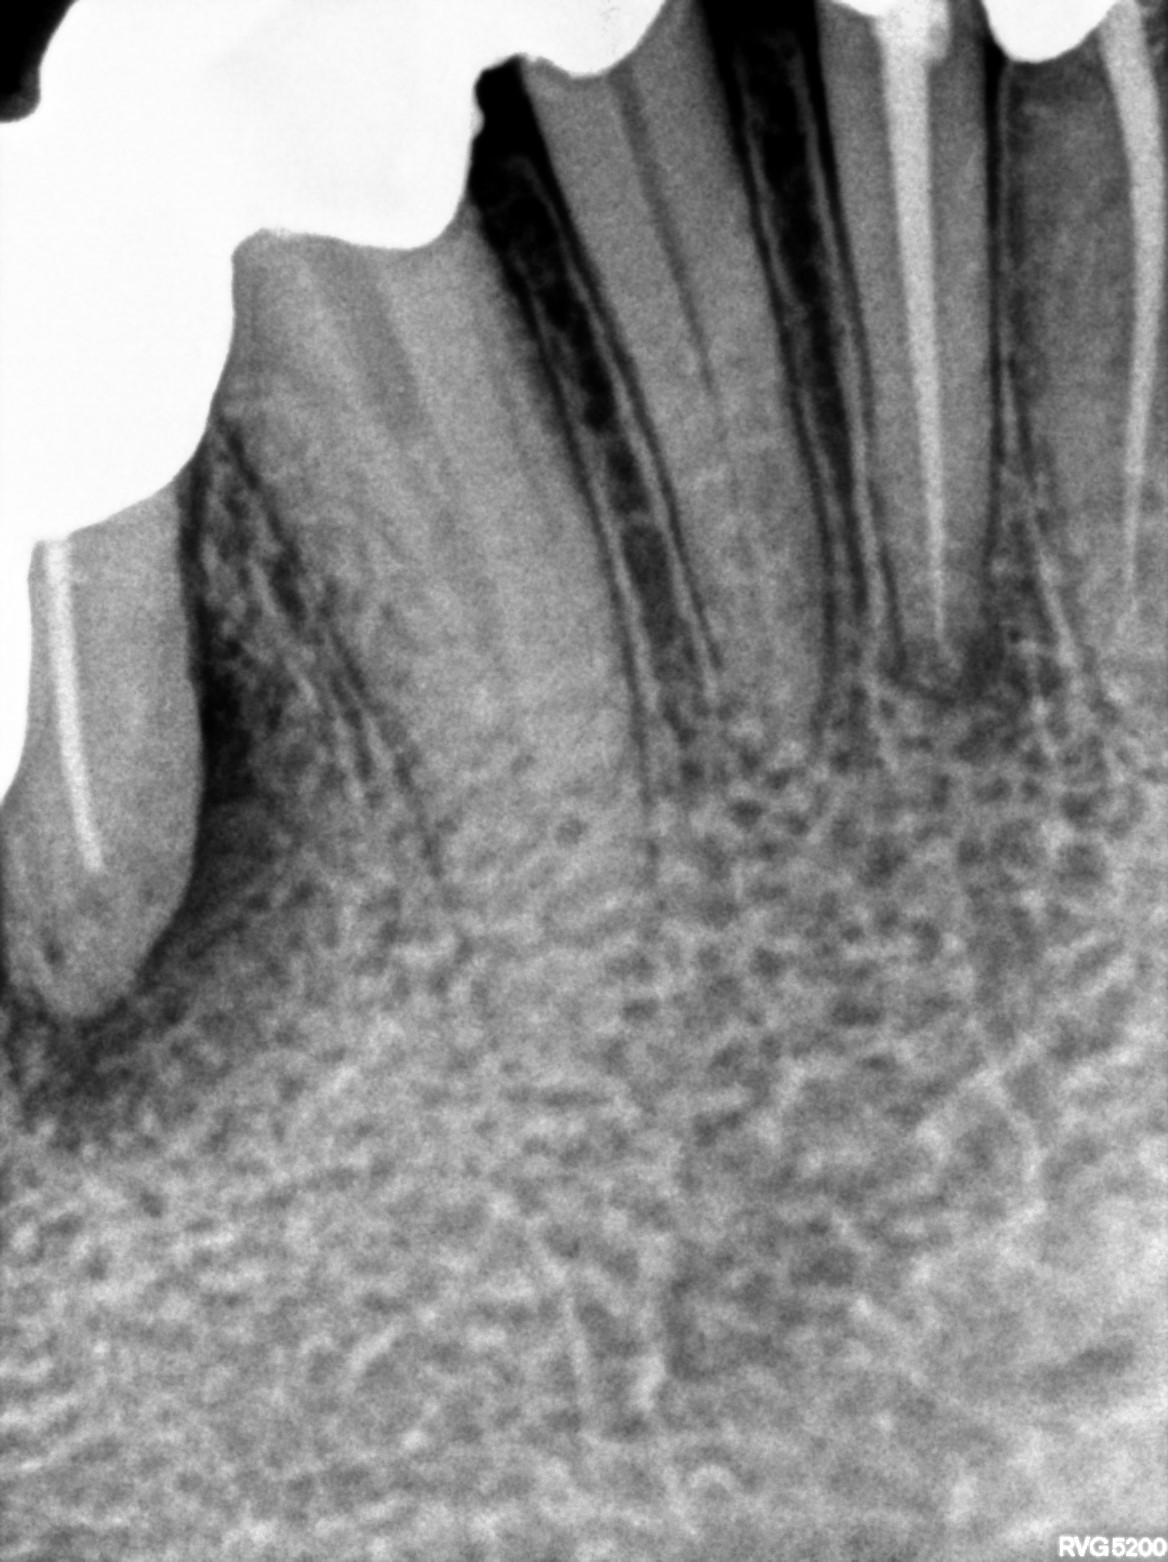

Dental Radiographs FHIR: DocumentReference · LOINC 24641-7

xray_1765005927_0.jpg

24641-7